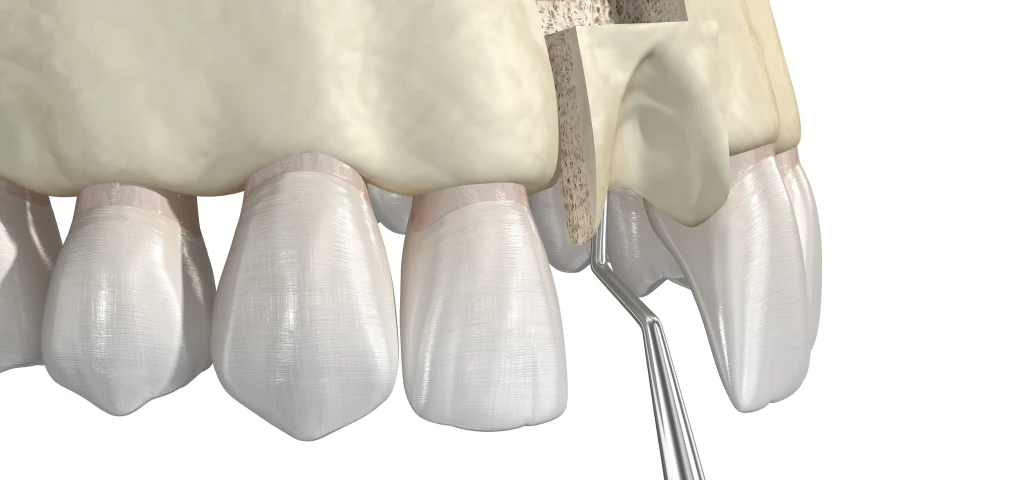

La chirurgie orale regroupe un ensemble d’interventions réalisées au niveau de la bouche, des dents et des mâchoires, allant de l’extraction des dents de sagesse aux actes plus complexes comme les kystes, les freinectomies ou les préparations implantaires.